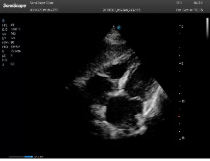

(2)搖:整個超聲探頭平面緊貼受檢區(qū)域皮膚,以超聲探頭與胸壁的接觸點為支點,將超聲探頭左右搖擺,觀察整個切面。

腰椎小關節(jié)